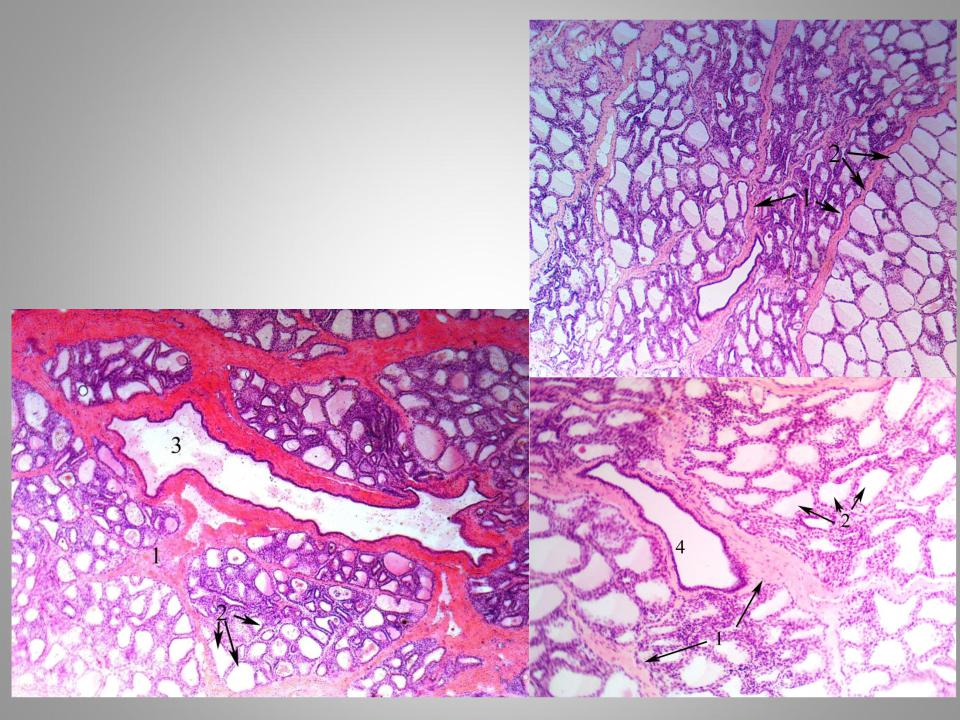

Исследование: микропрепарат молочной железы в медицине

Раздел: Снимки-откровения